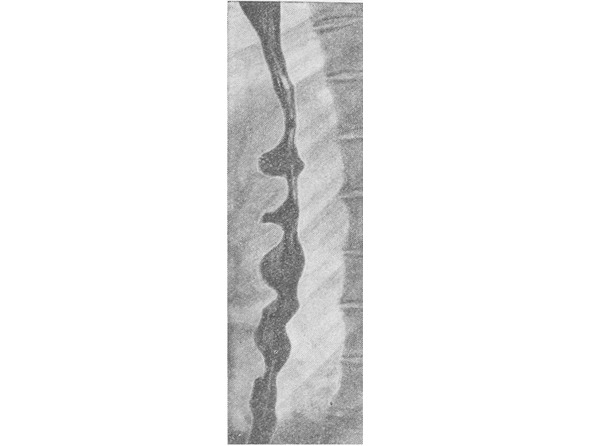

Рентгенологическое исследование (рентгеноскопия с гидроокисью бария) – выявляется:

– разнообразные спастические деформации пищевода:

• в виде четок, штопора (рис. 8),

• псевдодивертикулы (ложные дивертикулы),

• пищевод в форме сосуда с завинченной пробкой и т.д.;

– диаметр пищевода выше и ниже сужений не изменен;

– стенки пищевода эластичны;

– складки слизистой оболочки продольные;

– перистальтика неравномерная и нерегулярная.

При повторных рентгенологических исследованиях обычно сохраняется один и тот же тип нарушения перистальтики.

Рисунок 8. Рентгенограмма пищевода – сокращения пищевода, не связанные с перистальтикой, придают органу сходство со штопором